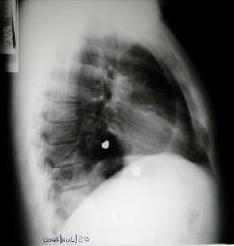

Rx. tórax (hace 6 meses), posterior al egreso de su antecedente traumatico.

Rx. Tórax al momento de su Ingreso. motivo de su referencia a nuestro hospital.